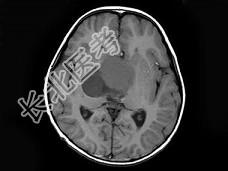

- 单项选择题女,51岁, 视力下降伴左侧面部麻木1个月,MRI检查如图所示, 应考虑为 ( )